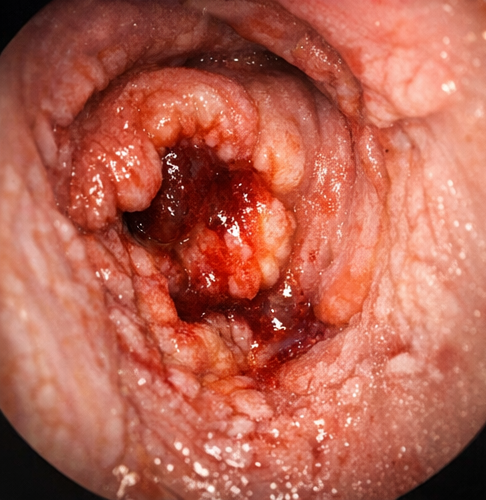

After hemodynamic stabilization, colonoscopy was performed. Multiple oval-shaped ulcers were observed in the terminal ileum, with one actively oozing lesion consistent with typhoid ulceration. No other source of bleeding was identified.